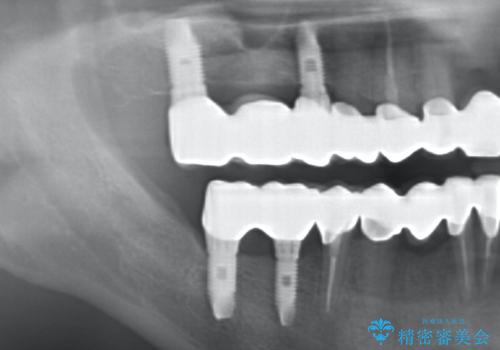

水銀を含む環境汚染金属アマルガムの除去 奥歯のセラミックインレー修復

- 古くなった銀歯を白くしたいとの希望で来院されました。

30年ほど前につめた水銀を使用する金属、アマルガム充填がなされていました。

アマルガムが飛散しないよう注意深く除去し、セラミックインレー修復を行います。

今回銀歯を白くされたいという希望でしたので、除去の際水銀を含むアマルガムが飛散しなよう細心の注意を払い、丁寧に除去したのちセラミックインレー(emaxプレスインレー)で審美的に修復を行いました。